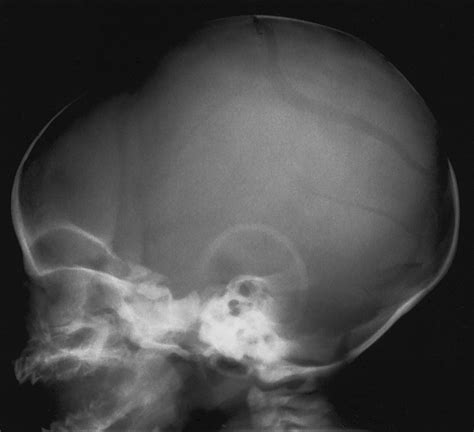

• Skull Shape: The shape of the skull can provide insights into developmental issues or deformities.

• Fontanelles: The soft spots on a baby’s skull, known as fontanelles, should be checked for proper closure and any signs of swelling or bulging.

• Sutures: The sutures, or the fibrous joints between the skull bones, should be examined for any signs of premature fusion or separation.

Several common findings can be identified through a Baby Skull Xray. Understanding these findings is essential for accurate diagnosis and treatment:

• Tumors: Abnormal growths or masses within the skull.

• Developmental Abnormalities: Issues with the development of the skull, such as premature fusion of sutures.